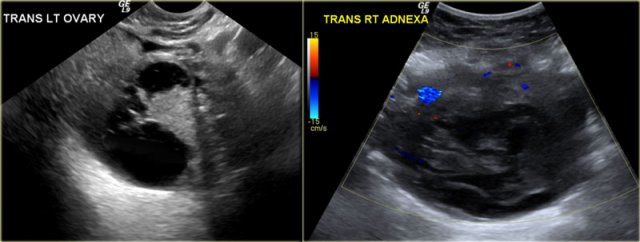

The transvaginal ultrasound images show a small complex ovarian cyst with wall vascularity on power Doppler analysis.

The characteristic circular Doppler appearance is called the 'ring of fire'.

Note, there is good through-transmission and no internal vascularity, consistent with a, partially involuted, corpus luteum cyst.

Corpus luteum cyst Corpus luteum cyst

Another case with the typical the 'ring of fire' on ultrasound.